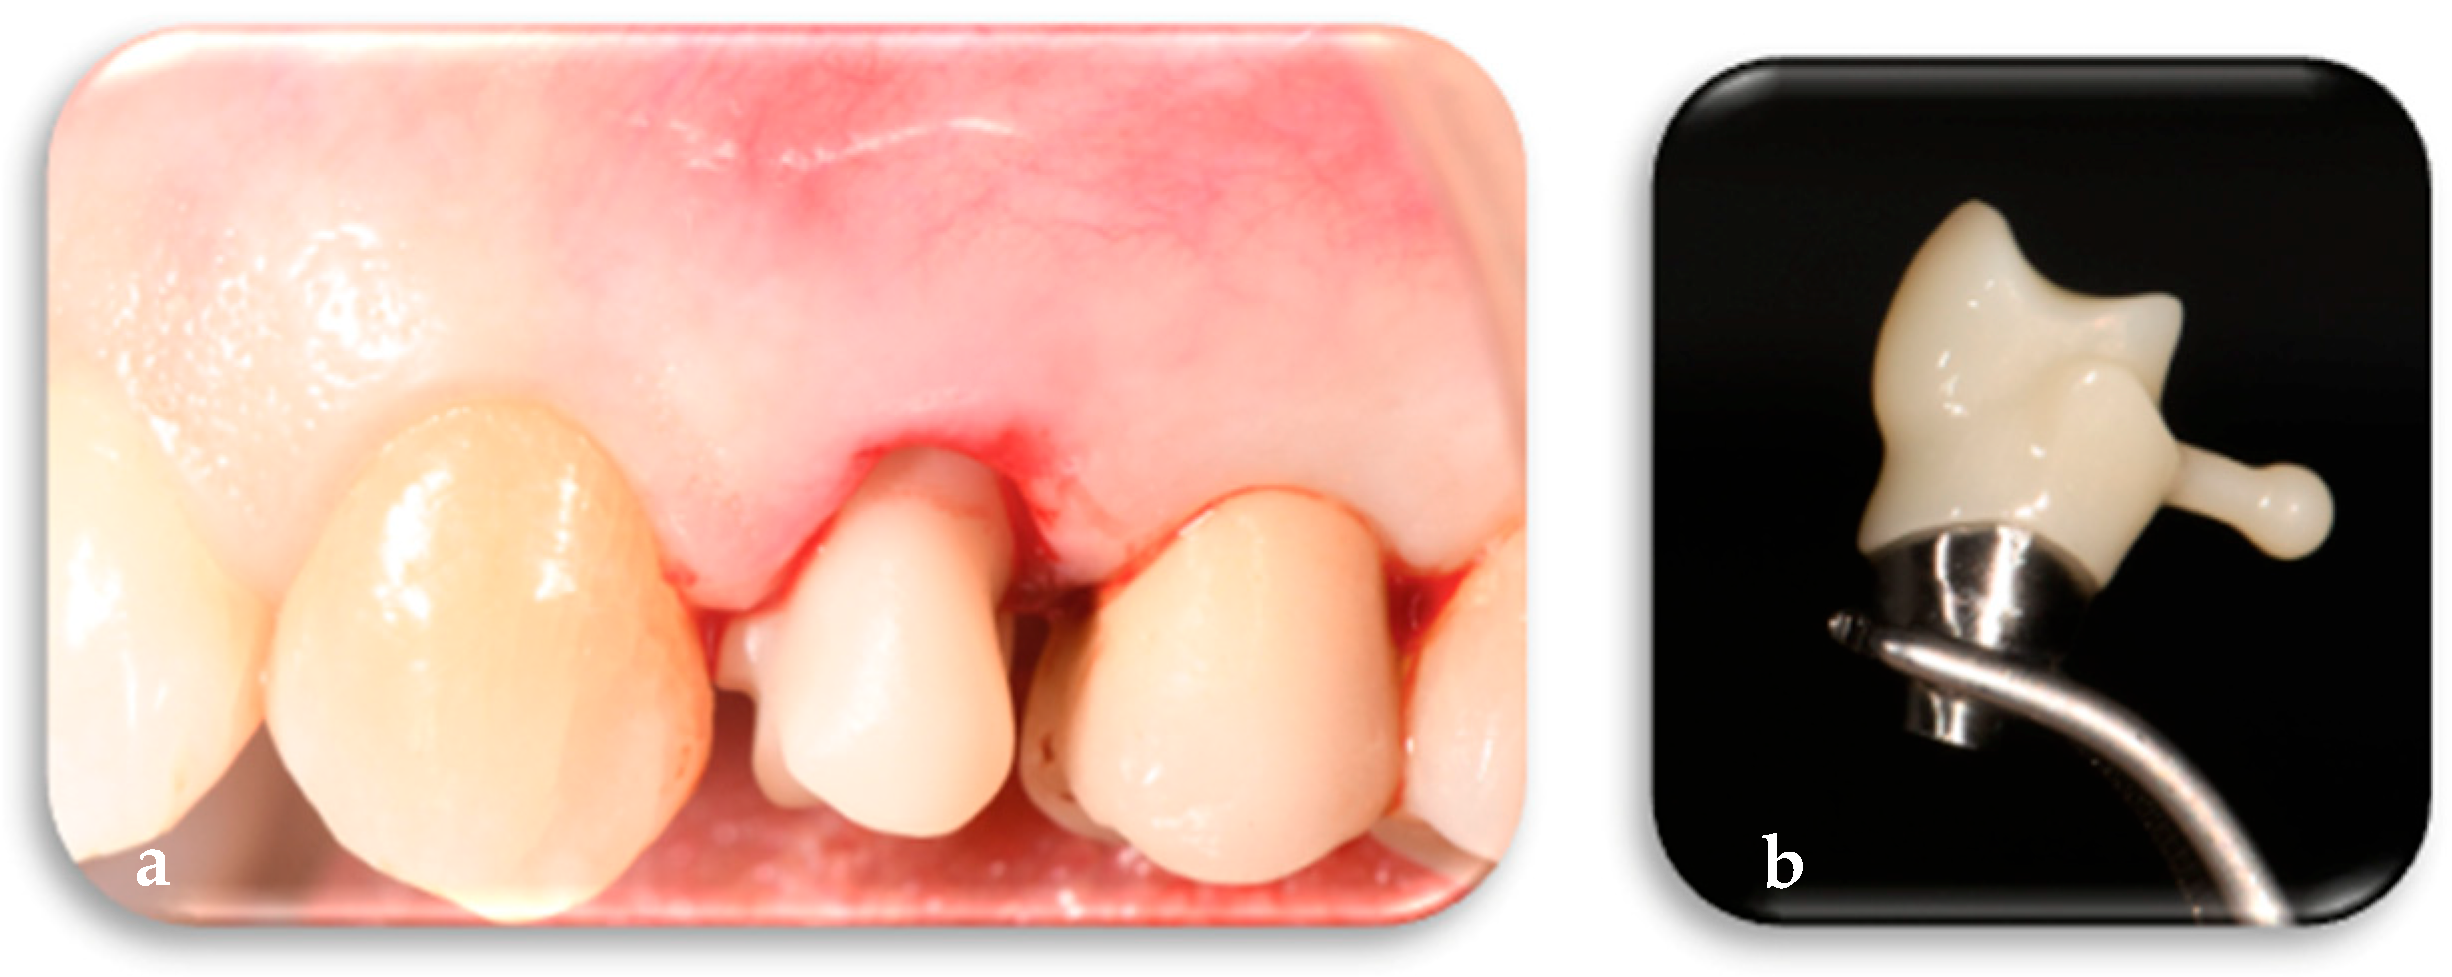

2.1.2. Phase 2: Implant Placement, Delivery of the Definitive Customized Abutment, Coping, Provisional Restoration, and Fitting of the Definitive Framework